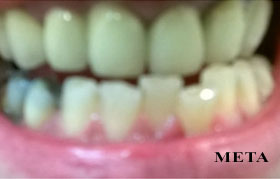

bonding δοντιών

άμεσες όψεις - edelweiss